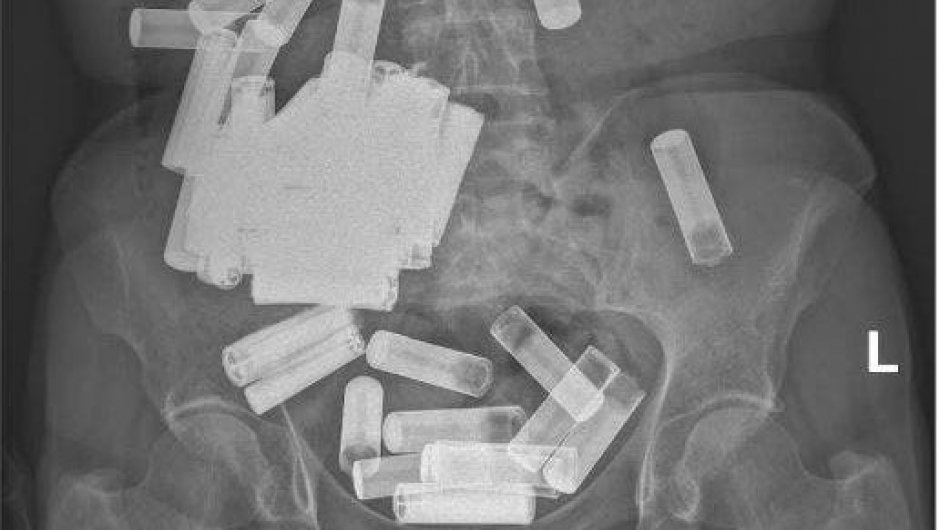

Desafortunadamente, una radiografía reveló una multitud de baterías en su abdomen, aunque afortunadamente ninguna parecía estar obstruyendo su tracto gastrointestinal y ninguna batería mostraba signos de daño estructural.

Durante un período de una semana, defecó cinco pilas AA, pero las radiografías tomadas durante las siguientes tres semanas mostraron que la gran mayoría de las pilas no habían podido seguir avanzando por su cuerpo. En ese momento, el paciente estaba experimentando dolor abdominal difuso.